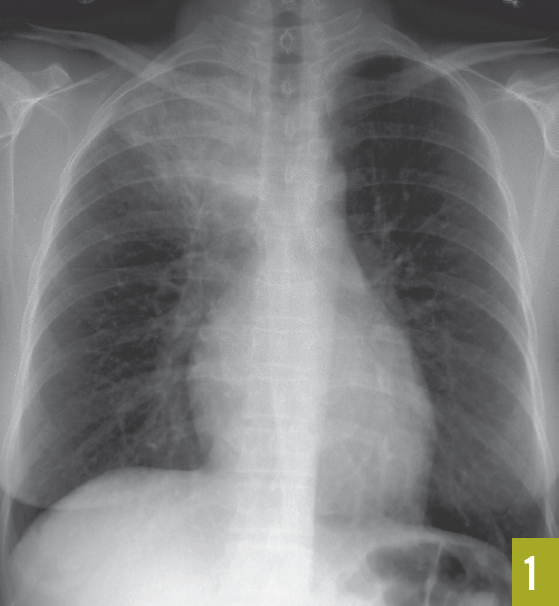

Meghana Halkar, MD; W.H. Wilson Tang, MD; Chadi Alraies, MD; Suzanne R. Lutton, MD; Martin N. Wiseman, MD

A 42-year-old man with no prior cardiac history presented to the emergency department after experiencing a syncopal episode a few hours after a 20-minute run.